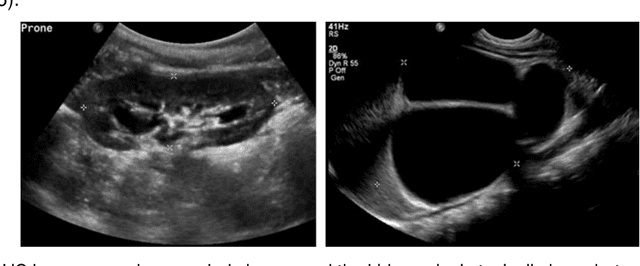

Abstract:It remains challenging to automatically segment kidneys in clinical ultrasound images due to the kidneys' varied shapes and image intensity distributions, although semi-automatic methods have achieved promising performance. In this study, we developed a novel boundary distance regression deep neural network to segment the kidneys, informed by the fact that the kidney boundaries are relatively consistent across images in terms of their appearance. Particularly, we first use deep neural networks pre-trained for classification of natural images to extract high-level image features from ultrasound images, then these feature maps are used as input to learn kidney boundary distance maps using a boundary distance regression network, and finally the predicted boundary distance maps are classified as kidney pixels or non-kidney pixels using a pixel classification network in an end-to-end learning fashion. Experimental results have demonstrated that our method could effectively improve the performance of automatic kidney segmentation, significantly better than deep learning based pixel classification networks.

Abstract:It remains challenging to automatically segment kidneys in clinical ultrasound (US) images due to the kidneys' varied shapes and image intensity distributions, although semi-automatic methods have achieved promising performance. In this study, we propose subsequent boundary distance regression and pixel classification networks to segment the kidneys, informed by the fact that the kidney boundaries have relatively homogenous texture patterns across images. Particularly, we first use deep neural networks pre-trained for classification of natural images to extract high-level image features from US images, then these features are used as input to learn kidney boundary distance maps using a boundary distance regression network, and finally the predicted boundary distance maps are classified as kidney pixels or non-kidney pixels using a pixel classification network in an end-to-end learning fashion. We also proposed a novel data-augmentation method based on kidney shape registration to generate enriched training data from a small number of US images with manually segmented kidney labels. Experimental results have demonstrated that our method could effectively improve the performance of automatic kidney segmentation, significantly better than deep learning based pixel classification networks.